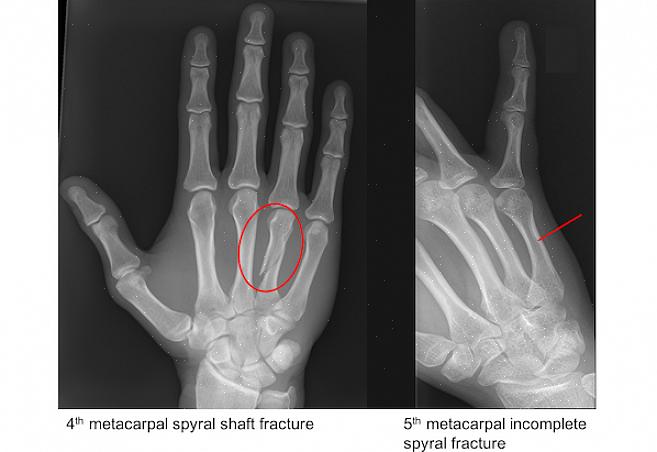

שבר מטקרפל

המונח 'שבר מטקרפל' מתייחס לשבר בכל אחת מחמש העצמות הללו. זה קורה לרוב במהלך ספורט. לדוגמה, בכדורסל, העצמות הללו משמשות ללא הרף כדי לכדרר את הכדור, לקבל מסירות או ליירט מסירות.